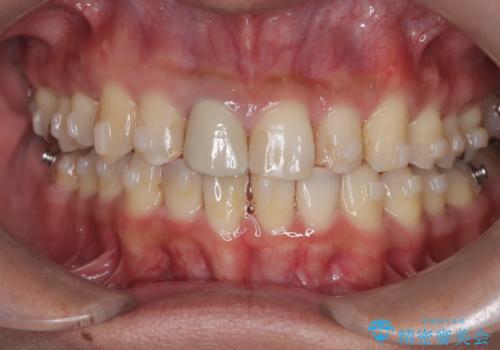

【インビザライン】八重歯と歯のでこぼこが気になる!

- 「八重歯と歯のでこぼこを治したい」を主訴に来院された患者様です。

歯は抜かずに奥歯の遠心移動とIPRで八重歯とでこぼこを改善しました。

左上3番は保険治療(CR)の劣化による二次カリエスになっていますので、後日治療予定です。